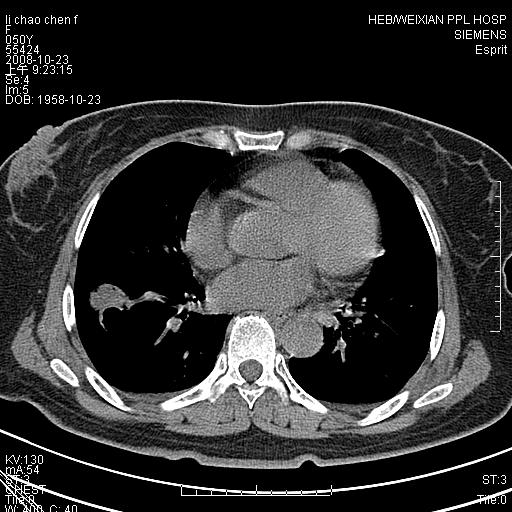

体检发现肺部肿块,现无不适。五年前曾有过哮喘病史。

先对现有的图象资料谈几点看法:病变位于右肺下叶前基底段,上部呈类圆形改变,分叶及毛刺征象不明显,下部呈不规则气腔改变,近肺门侧可见与一粗大血管相连,考虑为引流静脉影.其他肺叶相对正常所见.分析:该病灶良恶性均有可能.(现有资料来说).强化及穿刺活检有助鉴别.

考虑右肺下叶前基底段周围型肺癌可能性大。

右肺下叶前基底段占位性病变,不排除周围型肺癌可能,尽快手术为妙。

右肺下叶前基底段周围型肺癌可能性大。